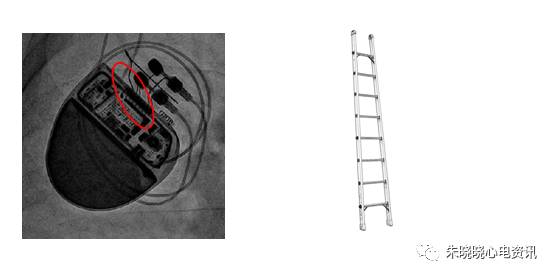

另有部分起搏器接线方式像长梯(图10)

图10 波士顿科学起搏器

索林的起搏器接线方式像短梯(图12)

图12 索林起搏器